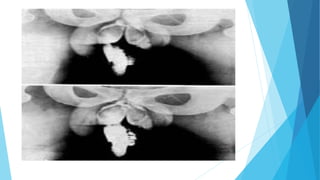

Técnica radiográfica consistente en la opacificación, mediante un medio de

contraste y por vía retrógrada, de los conductos deferentes, obteniendo

imágenes con fines diagnósticos.

Desembocadura ectópica del uréter izq

Radiodiagnóstico. Técnica radiográficaconsistente en la opacificación, mediante un medio de contraste y por vía retrógrada, de los conductos deferentes, obteniendo imágenes con fines diagnósticos.